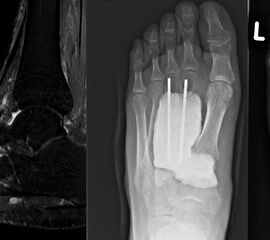

Bei der operativen Therapie maligner Neoplasien ist im Rahmen eines kurativen Therapie­ansatzes die weite Resektion zwingend erforderlich. Dabei richtet sich das jeweilige operative Vorgehen mit der nachfolgenden Rekonstruktion nach der Lokalisation des Tumors. Bei Läsionen im Bereich der distalen Tibia ist eine Segmentresektion des Knochens mit möglicher Überbrückung des Defekts durch Verwendung eines Tibia-Verschiebespans oder Fibula-Autografts und gleichzeitige Arthrodese im Bereich des oberen Sprunggelenks möglich. Aufgrund der hohen Belastung in diesem Extremitätenabschnitt ist eine Doppelung der Fibula und Anlagerung zusätzlicher Beckenkammspongiosa zu diskutieren (Burgkart, 2003). Bei Neoplasien im Bereich der distalen Fibula kann mit segmentaler Resektion des betroffenen Knochenabschnitts inklusive lateralem Malleolus und Durchführung einer tibio-talaren Arthrodese mit geringgradiger Extremitätenverkürzung meist ein funktionell gutes Ergebnis erzielt werden. Ist der Knochentumor im Bereich der posterioren Talusanteile lokalisiert so kann nach Osteotomie im Bereich des Talushalses unter Verkürzung der Extremität eine tibiocalcaneare Arthrodese mit Einbeziehung des restlichen Talus im Sinne einer Blair-Arthrodese durchgeführt werden 28. Bei Tumoren im Bereich des Calcaneus, die eine weitere Resektion notwendig machen, ist entweder eine Syme-Amputation oder die isolierte Resektion des Calcaneus mit Versorgung des entstandenen Defekts durch einen myo-cutanen Lappen und Verwendung spezieller Schuhe möglich (Burgkart, 2003). Ausgeprägte Befunden, die über die Höhe des oberen Sprunggelenks hinausreichen, erfordern selten eine distale Unterschenkelamputation (Abb. 10a-e). Die früheren Amputationsschemata, die von Amputationen in der distalen Hälfte des Unterschenkels abgeraten haben, besitzen heute keine Gültigkeit mehr 29. Dem Erhalt der Länge ist nach Beachtung einer entsprechenden Radikalität der Tumorresektion höchste Priorität zu bemessen. Bei Tumorlokalisation im Bereich des Mittelfußes können nach vollständiger Entfernung des jeweiligen Knochens Rekonstruktionen unter Verwendung autologer oder allogener struktureller Transplantate ("strut grafts") zu funktionell guten Mittelfußarthro­desen führen (Abb. 11) (Burgkart, 2003). Mit Ausnahme der großen Zehe können Amputationen der Zehen meist gut kompensiert werden. Amputationen in Höhe der Grund- und Mittelglieder der Kleinzehen sind wegen der Imbalance der Muskulatur mit sekundären Fehlstellungen zu vermeiden 29.

Hierbei wird der Tumor mit einem entsprechenden Sicherheitsabstand, also einem Mantel gesunden Gewebes entfernt. Eine genaue Definition des notwendigen Abstands in Zenti­metern ist kaum möglich da unterschiedliche Gewebearten eine unterschiedliche Barriere für Tumorzellen darstellen. Weite Resektionen für mittel- oder schlechtdifferenzierte Malignome sind aufgrund des geringen Weichteilmantels über dem knöchernen Skelett im Bereich des Fußes und Sprunggelenks mit onkologisch ausreichendem Abstand und dennoch innerhalb des Kompartiments selten sinnvoll durchführbar. Bei größeren Tumorausdehnungen müssen häufig weite Anteile der Weichteildeckung reseziert werden was plastisch-chirurgische Deckungen nach sich zieht. Ist ein primärer Wundverschluß nicht möglich, so werden ent­sprechende Defektwunden zwischenzeitlich häufig per Vacuumversiegelung verschlossen bis die histopathologische Analyse abgeschlossen ist und einen mikroskopisch vollständigen Resektionsstatus im Gesunden (R0) bestätigt (Abb. 12 und 13).